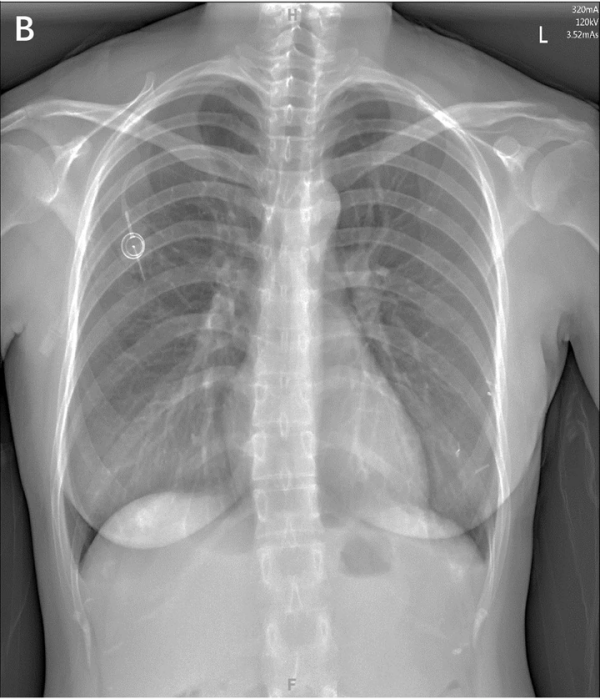

1胸壁港

胸壁港最常见的是经『颈内静脉』或『锁骨下静脉』置入[2-3]

▲ 胸壁输液港的方式及对比